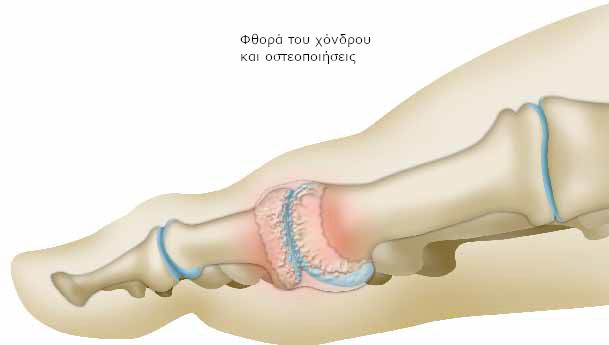

Η μαλακή επιφάνεια, που καλύπτει τα οστά (χόνδρος) στην άρθρωση του μεγάλου δακτύλου (μεταταρσοφαλαγγική άρθρωση) φθείρεται.

Οι άκρες του μεταταρσίου και της πρώτης φάλαγγας δεν ολισθαίνουν ομαλά μεταξύ τους.

Το οστό χάνει την προστατευτική επιφάνεια του χόνδρου, λόγω της φθοράς. Τα οστά έρχονται σε άμεση επαφή και προκαλούνται τριβές κατά την κίνηση της άρθρωσης.

Όσο η ασθένεια εξελίσσεται, το οστό παραμορφώνεται. Στις άκρες του δημιουργούνται οστικές προεξοχές (οστεοποιήσεις ή οστεόφυτα).